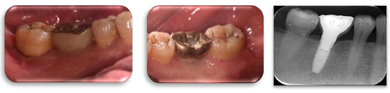

术后1年,47远中及颊侧中央PD 3~5 mm,BI1,颊侧中央根面得到覆盖,X线片示47远中骨缺损明显修复,患者的咬合不适基本得到缓解(图17,图18,图19)。